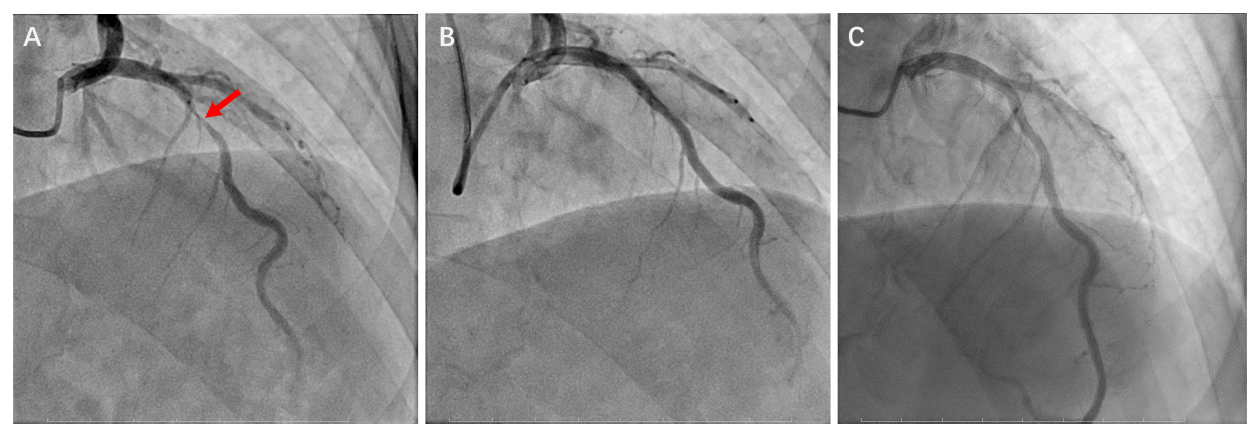

不久前,王老伯因肺部肿瘤入住胸科医院,准备接受外科手术。然而术前冠脉CTA检查发现了更为凶险的情况:左前降支近段重度狭窄达90%!这是心脏供血最重要的一根血管,老人随时可能发生心梗甚至猝死。

如果先处理心脏,传统冠脉支架植入后,需要服用抗血小板治疗至少3个月,等待意味着肿瘤进展、转移的风险与日俱增。如果先切肿瘤,术中心脏随时可能“罢工”,患者有生命危险。面对这一两难抉择,胸科医院心内科、胸外科、麻醉科专家进行了多学科会诊,决定采用药物球囊血管扩张成形术解决心脏问题。介入术后不久,王老伯又顺利接受了肺部肿瘤切除术。最近,他来医院复查显示,肺和心脏的状况都很好。